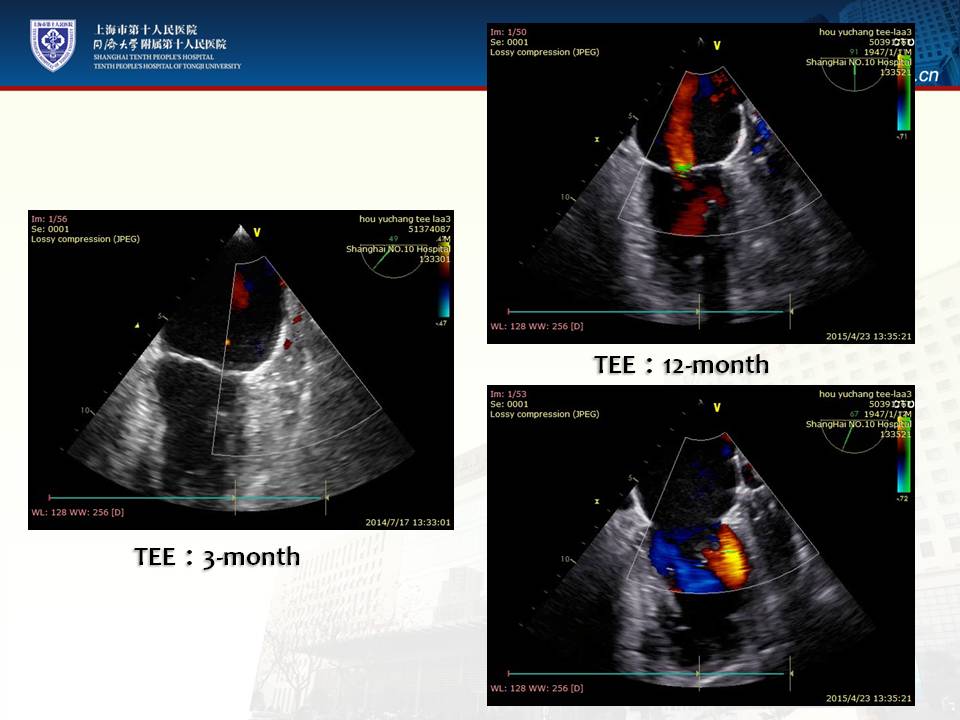

左心耳封堵术后抗凝:经验与证据